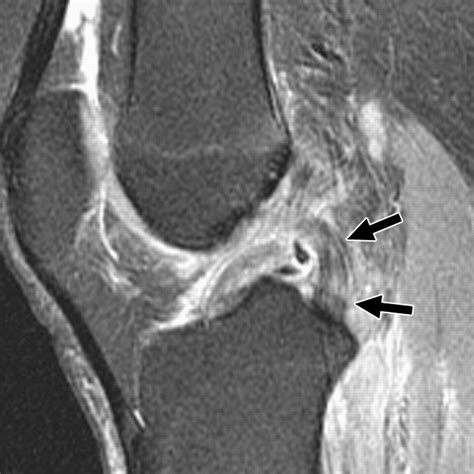

To confirm a Post Cruciate Ligament Tear, physicians typically perform a physical examination, including the "posterior drawer test," where they push on the tibia while the knee is bent to assess for excessive backward movement. Imaging, such as an MRI, is usually required to visualize the ligament clearly and rule out accompanying fractures or cartilage damage.

• posterior cruciate ligament tear mri